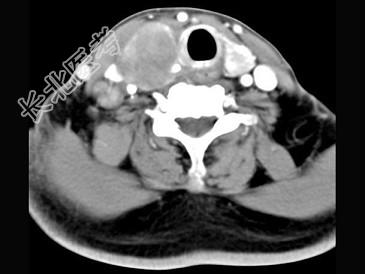

- 多项选择题女,54岁, 右侧颈部肿大近1年,近来病人有声嘶、吞咽困难, CT扫描如图,正确的描述或诊断是 ( )

A、右侧甲状腺肿大,密度减低

B、增强扫描示甲状腺呈不规则强化团块影,其内有低密度区,病灶境界不清

C、右侧颈内静脉增粗,其内可见不规则充盈缺损区

D、甲状腺癌

E、右侧颈内静脉瘤栓形成